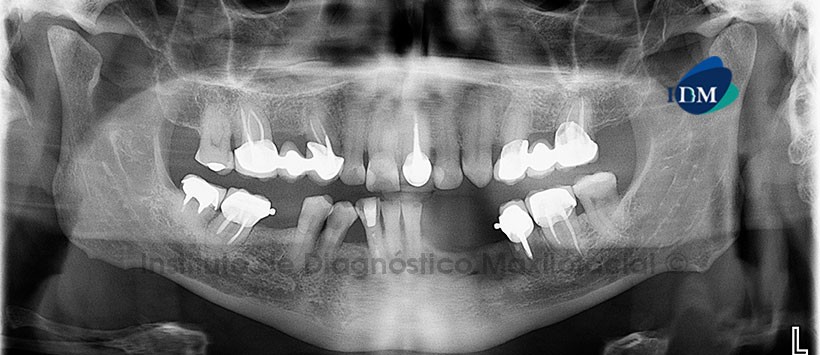

A la evaluación de la radiografía panorámica se aprecia múltiples piezas con tratamiento de conductos y con restauraciones protésicas coronales. Se evidencia defecto óseo a nivel de las piezas 3.4, 3.3, y 3.2 compatible con probable defecto pos quirúrgico. Ausencia de pieza 1.3, se aprecia una imagen radiopaca de densidad dentaria proyectada sobre el seno maxilar derecho compatible con probable pieza dentaria (Figura 1).